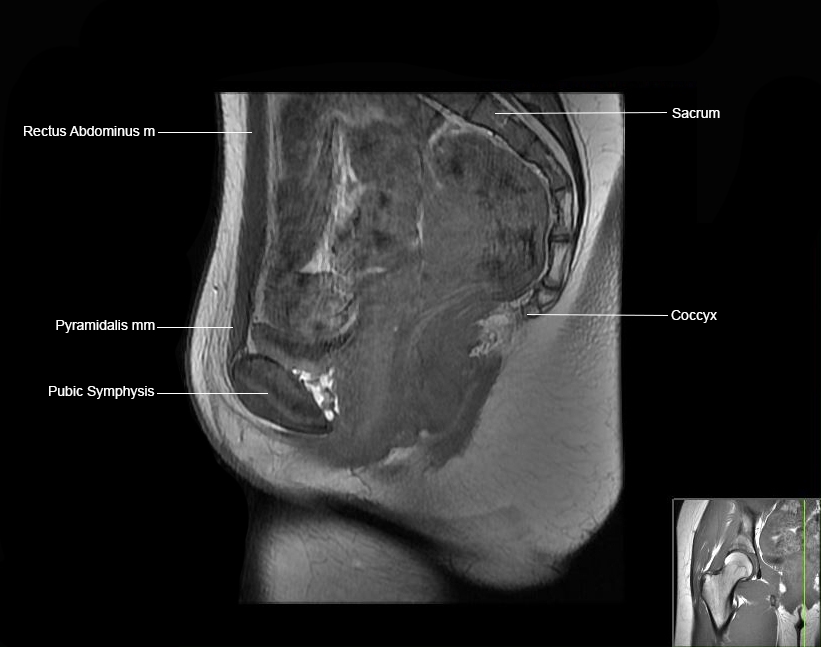

Hip

Basic Hip MRI

MRI Hip Anatomy

Scroll using the mouse wheel or the arrows